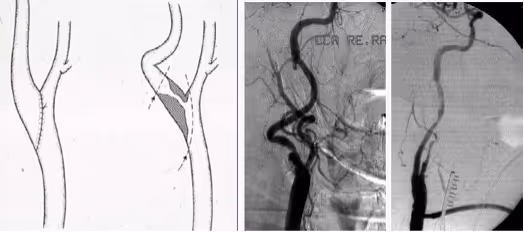

Eversion endarterectomy of the carotid bifurcation is an alternative to conventional endarterectomy. For this procedure, the ICA is transected at its origin and the plaque is removed as a cylinder by everting the ICA. The ICA is then reanastomosed to the bifurcation, without the use of a patch. In contrast to conventional endarterectomy, a shunt can only be inserted after eversion endarterectomy is completed.